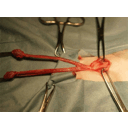

castration.jpg